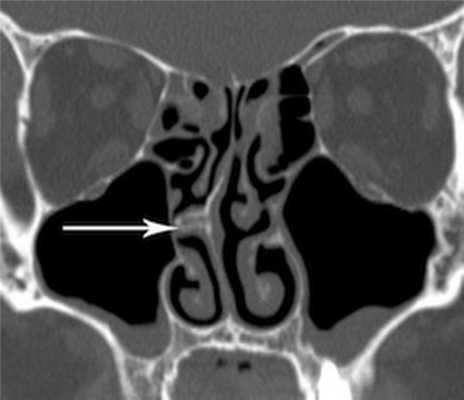

(Слева) На корональной КЛКТ (реконструкция) визуализируется добавочное переднее устье.

(Справа) На корональной КЛКТ визуализируются добавочные устья В, расположенные за основными. Картина сопоставима с таковой после хирургического вмешательства по поводу хронического синусита. Определяется утолщение слизистой оболочки В обеих верхнечелюстных пазух, обусловленное хроническим воспалением.